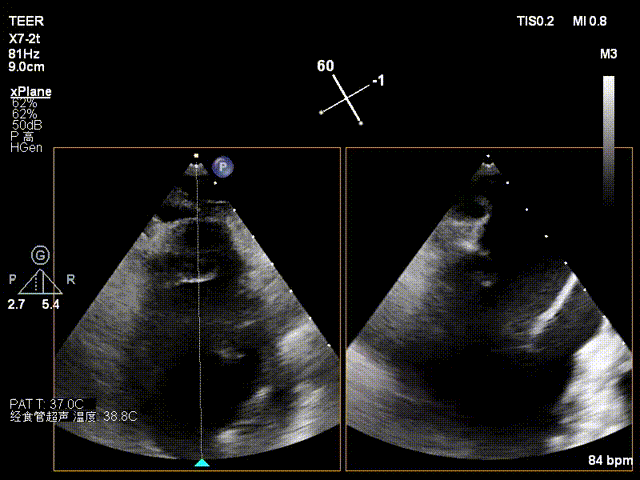

X-plane2区

经食道超声检查提示:二尖瓣瓣叶增厚冗长2区后瓣脱垂呈连枷样改变,考虑Barlow’s综合征。评估解剖结构:前叶长度:3.3cm,后叶长度:2.8cm,脱垂宽度:26mm,脱垂高度:19mm,瓣口面积:7.5cm²。

X-plane 1区

X-plane 2区